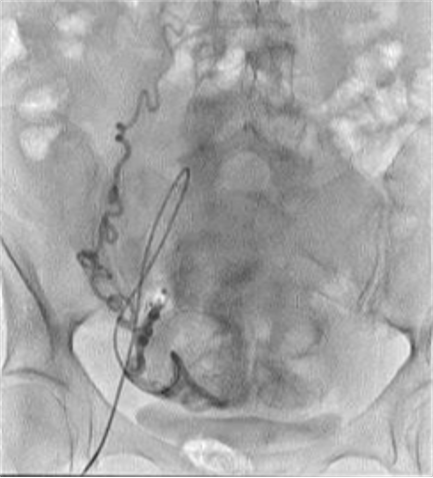

![]() 双侧子宫动脉发育不良 双侧卵巢动脉栓塞术 - 500 - 900 微米 未出现卵巢功能衰竭 ![]() 约10%-15%的患者在接受UAE后未见明显改善,其中一些病例可能是因为卵巢动脉提供了额外的血供。 文章通过回顾六例患者的治疗经验,探讨了卵巢动脉栓塞术(OAE)作为子宫动脉栓塞术(UAE)补充疗法的可行性和效果。研究发现,OAE能够成功地使肌瘤缺血坏死,并且大多数患者在术后症状有所改善。尽管存在技术挑战,但OAE似乎是安全有效的。此外,所有接受OAE治疗的患者均保留了正常的月经周期,这表明该手术可能不会导致卵巢功能丧失。然而,由于样本量较小,目前的研究结果尚不足以得出明确结论,需要进一步的研究来验证这些发现。 ![]() 评估在有卵巢动脉参与供血的症状性子宫肌瘤患者中,进行卵巢动脉栓塞术的安全性及临床结局。 共13名患者,均有症状性子宫肌瘤,且MRI或血管造影显示有卵巢动脉参与供血。并在初次或二次进行补充卵巢动脉栓塞术。

所有年龄超过 40 岁的患者, 卵巢受损 14%-43% 研究中闭经发生率(15%)与单纯UAE报告相似,可能与患者年龄(≥45岁)及卵巢储备自然下降有关。 ![]() 50岁,长期因子宫肌瘤导致月经出血过多,痛经和贫血。 子宫肌瘤栓塞术前,显示双侧子宫动脉发育不全,子宫肌瘤双侧卵巢动脉。 经皮股动脉穿刺双侧卵巢动脉栓塞,先500μm-700μm emboSphere 微球 术后4周,和6月的中短期随访,月经正常,子宫容积减少,贫血纠正,无卵巢功能衰竭。但看起来非灌注容积较少。 术后9月,由于子宫肌瘤持续存在,患者自己希望绝经,行全子宫和双侧卵巢切除术 术后病理,子宫内可见栓塞微粒伴有坏死,卵巢内也见栓塞微粒,但卵巢功能未受损。